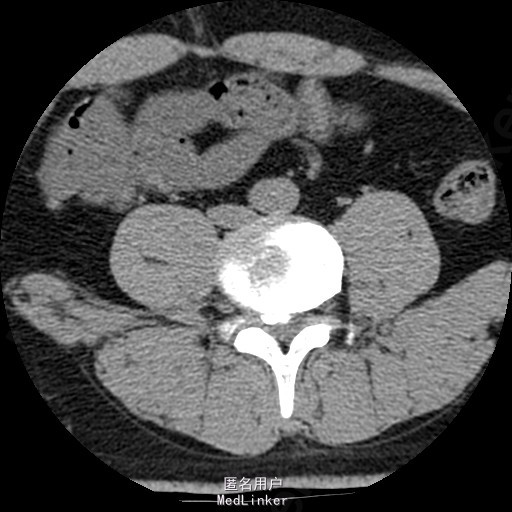

查体:腰部叩痛,腰部活动受限,左侧膝内侧、小腿外侧、内踝、足部感觉减退,右侧小腿、足背感觉减退,屈髋、伸膝、踝背伸肌肌力左侧4级,右侧4-5级,踇背伸、跖屈肌肌力左侧3-4级,右侧4级,双侧膝腱反射+,跟腱反射+,双侧巴氏征阴性,直腿抬高试验左侧40°阳性,右侧阴性。 辅助检查: X-ray:腰椎退行性变,多节段不稳 CT:腰椎间盘突出并椎管狭窄伴钙化,腰2-3,3-4,4-5,腰5骶1 MR:腰椎间盘突出并椎管狭窄,腰2-3,3-4,4-5,腰5骶1 上传受限无法全部上传,见谅

诊断:腰椎间盘突出症并椎管狭窄 处理: 1、完善相关辅助检查,明确诊断,有无手术指证; 2、完善手术评估,有无手术禁忌,手术风险及并发症; 3、在全麻下行腰椎后路多节段减压椎间植骨融合内固定术 4、腰2-3,腰3-4行开窗减压,腰4-5,腰5-骶1行椎间Cage植骨融合